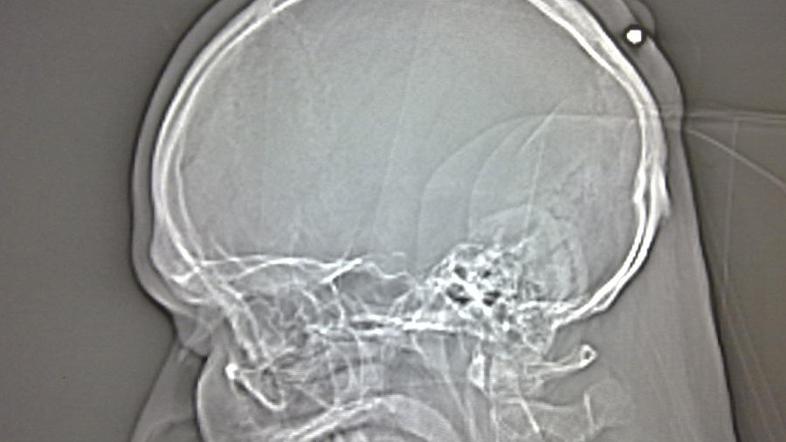

Neki Poljak, ki živi v Nemčiji, se pet let ni zavedal, da je bil ustreljen v glavo. Razlog: v času, ko ga je zadela krogla, je bil preveč pijan.

Policija iz mesta Bochum je sporočila, da so zdravniki pri 35-letnem Poljaku naboj v zadnjem delu glave našli potem, ko je bil ta prepričan, da mu bodo na operaciji odstranili cisto.

Ko pa so mu pokazali 5,6-milimetrski naboj, pa se je spomnil, da ga je na praznovanju novega leta "leta 2004 ali 2005" nekaj zadelo v glavo, ampak je na to pozabil, ker je bil "čisto pijan", je dejal tiskovni predstavnik policije.

"Povedal nam je, da se spomni glavobola, ampak se na to ni oziral in prav tako ni obiskal zdravnika," je še dejal tiskovni predstavnik. Sčasoma se je nato okoli naboja razvila večja rana, moški pa se je za operacijo odločil šele po dolgotrajnih bolečinah.

Ker obstaja velika verjetnost, da je moškega naboj, ki ga je nekdo med praznovanjem novega leta ustrelil v zrak, zadel naključno, policija preiskave ne bo sprožila. 35-letnik bo bolnišnico zapustil v petek.